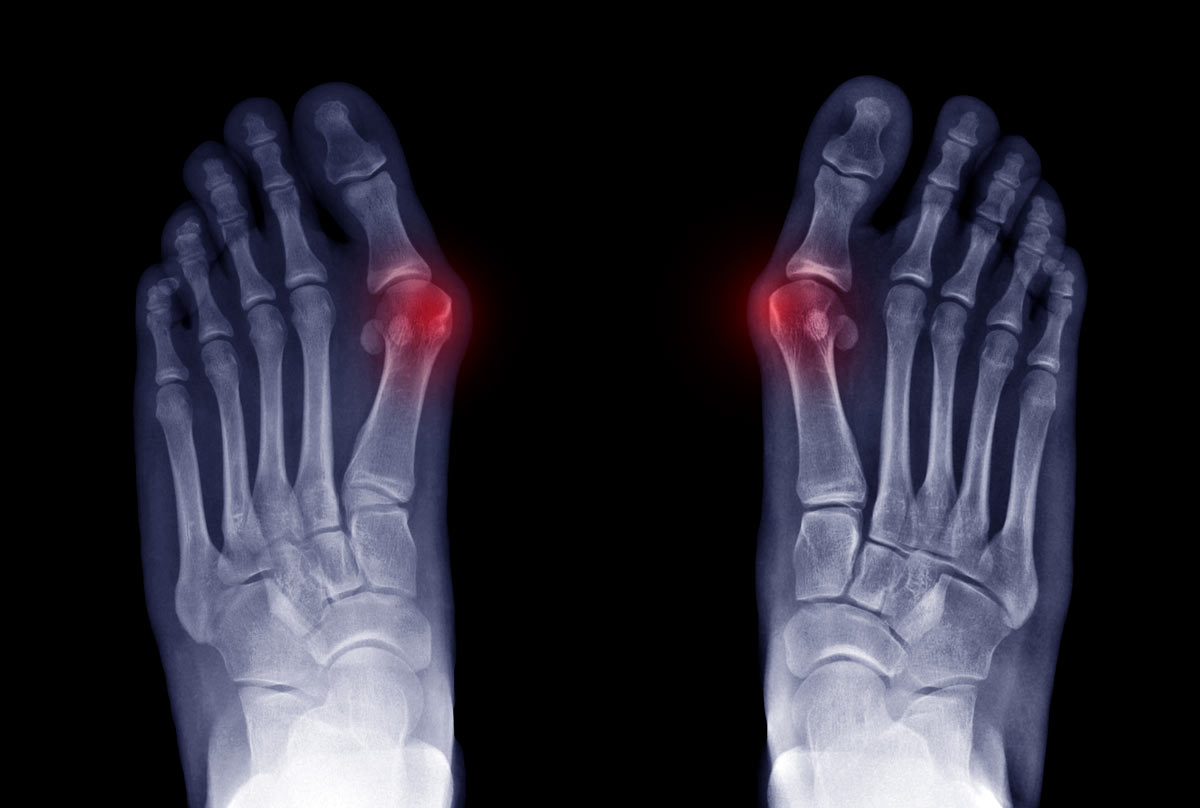

Dr. George Williams is not only a board-certified podiatrist serving the Palm Harbor community—he's a recognized innovator who has contributed to advancing the field of foot and ankle surgery. His pioneering work spans wound healing techniques, surgical evaluation tools, and precision-guided procedures that improve patient outcomes across Florida and beyond.

Explore Dr. Williams' innovative techniques that have advanced wound care through clinical research, surgical precision, and evidence-based treatment protocols.